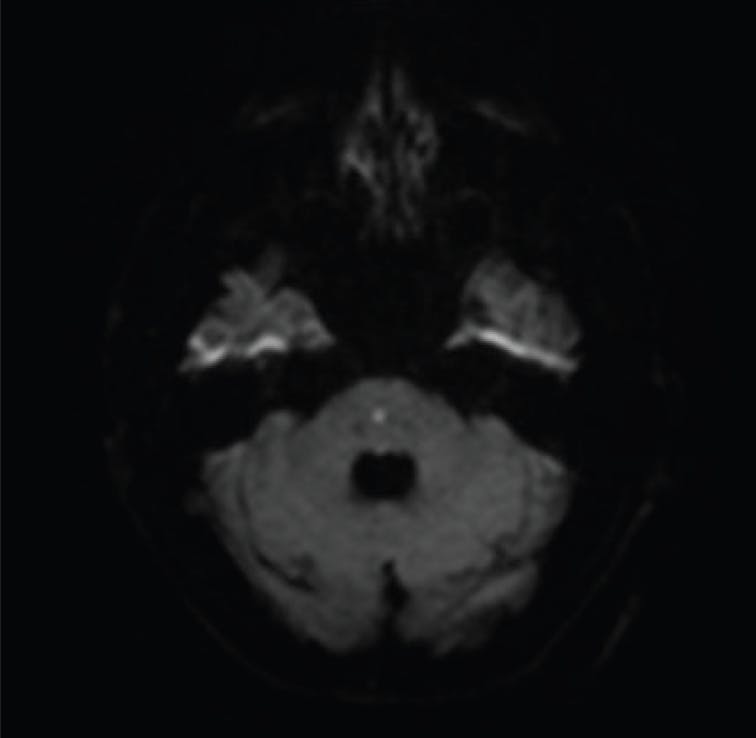

A 60-year-old male presented with diplopia after being discharged from the hospital with a normal CT scan of the brain and poor control of his cardiovascular disease. Examination revealed a very large vertical skew deviation, lack of superior oblique isolation on the Parks-Bielschowsky Three Step Test, and binocular torsion complaints. I asked the radiologist to focus on the brain stem in the MRI, which revealed a “tiny acute infarct in the central aspect of the pons” (Figure 6).